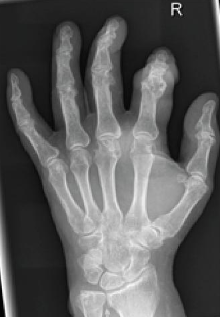

Nicht immer lässt sich die Diagnose einfach stellen. Besonders dann, wenn nicht das typische Metatarsophalagealgelenk I (klassische Podagra) betroffen ist oder wenn symmetrisch erscheinende Schwellungen und Entzündungen von z. B. den Hand- oder Fingergelenken auftreten (Abbildung 1). Vor allem bei jahrelang unbehandelter Gicht führen fortschreitende Harnsäurekristall-Ablagerungen zu Tophi (Abb. 2 und 3).